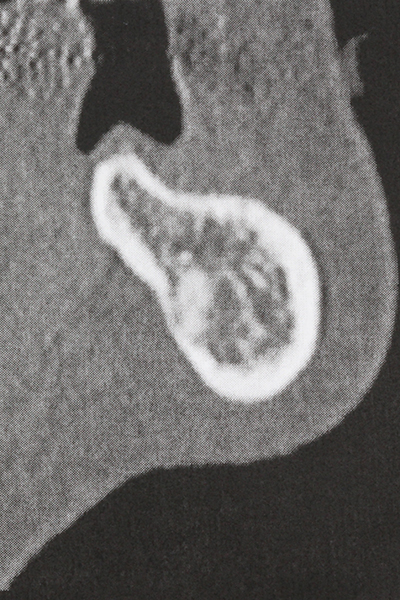

Preparation of the lateral window during an external sinus floor elevation is challenging, particularly for implantologists with little surgical experience. Removal of the bone cover of the sinus without injuring the underlying Schneiderian membrane is only part of the operation – after establishing an adequate access, the membranous lining of the sinus must be carefully mobilized to make space for the augmentation materials or the implants. Piezo surgery is useful for this indication in two ways: diamond-coated instruments can be used for selective bone ablation and the underlying mucous membrane remains intact when the procedure is done carefully. The ultrasonic frequencies also enable detachment of the mucous membrane without complications – the frequencies are transmitted into the space between the mucous membrane and sinus floor by special blunt attachments (Cassetta, Ricci et al. 2012, Pereira, Gealh et al. 2014) (Rickert, Vissink et al. 2013). As a result, it is not surprising that current reviews of external sinus floor elevation positively evaluate the use of piezoelectric devices as well as the use of roughened implant surfaces and bone replacement materials (Wallace, Tarnow et al. 2012).